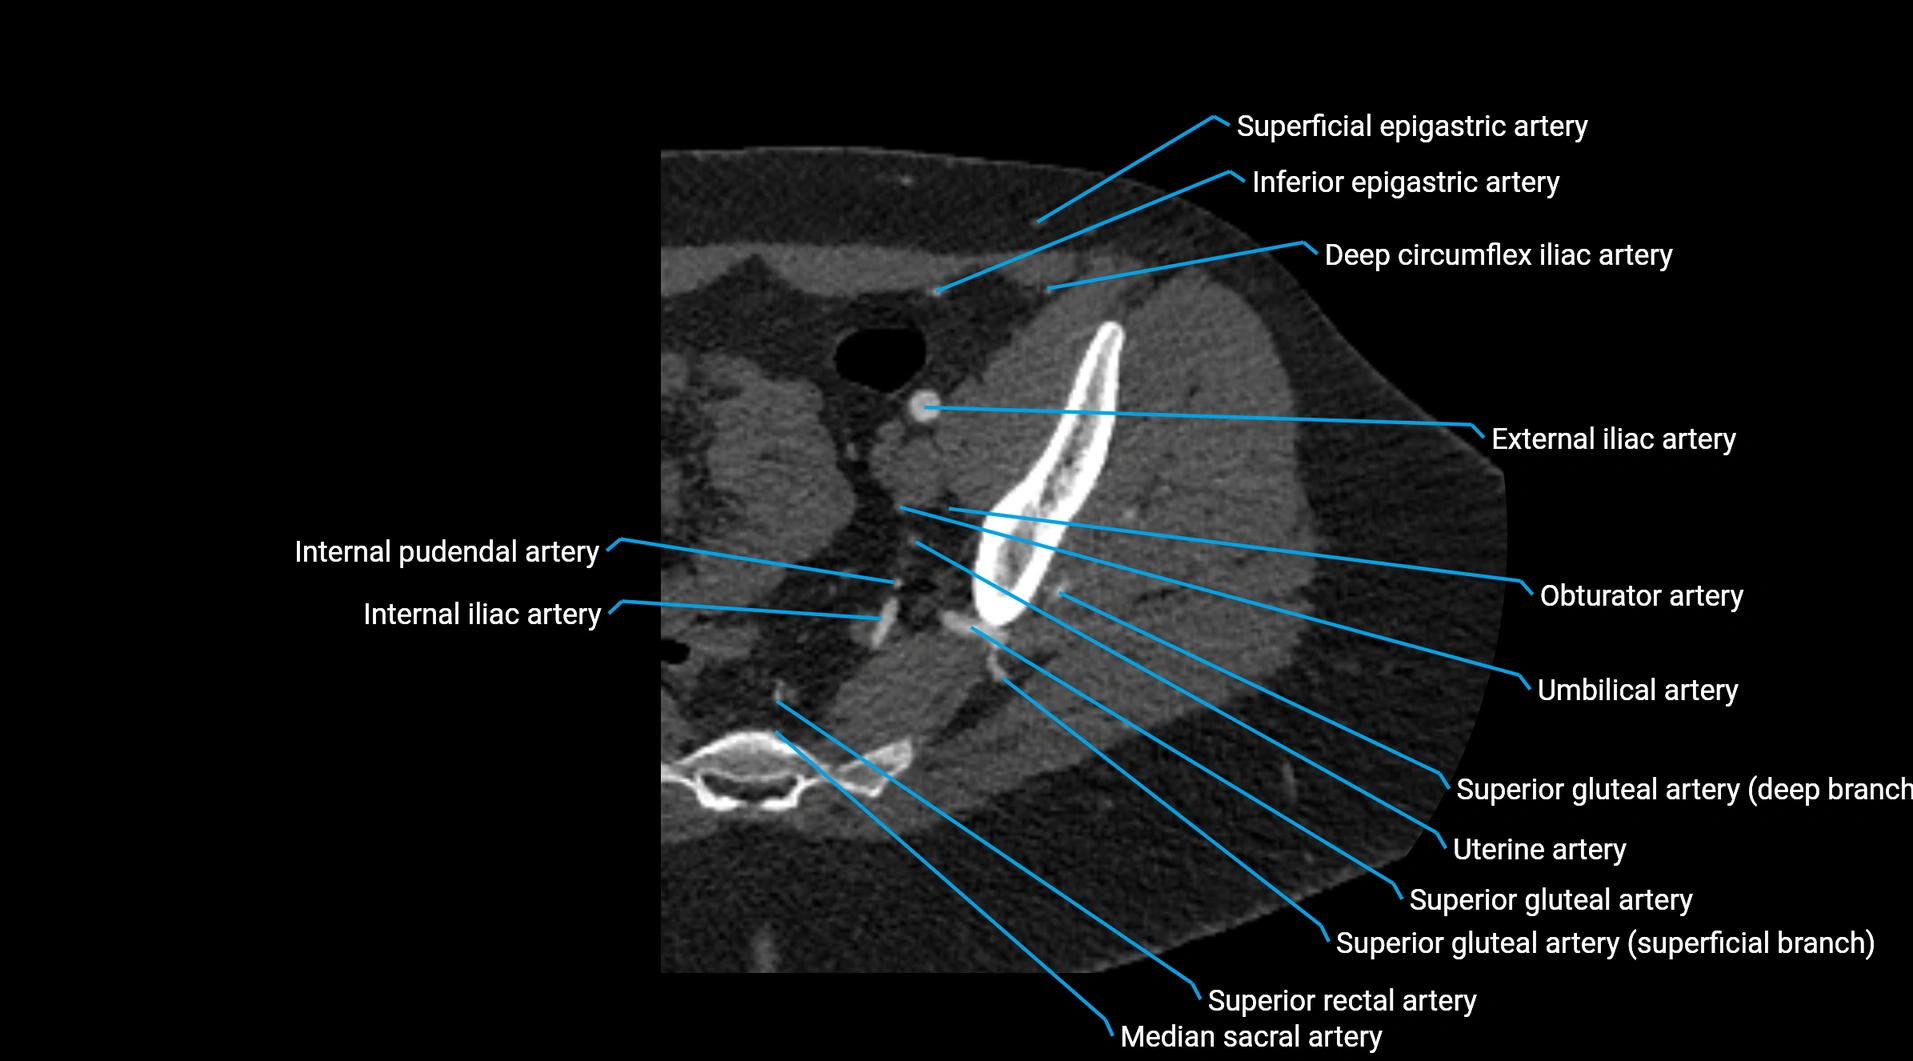

CT images

image

Contrast-enhanced CT (CTA):

• Gold standard for abdominal aortic imaging

• Provides excellent detail of lumen, wall, aneurysm, thrombus, and branch vessels

• Multiplanar and 3D reconstructions help in aneurysm measurement, stent graft planning, and dissection evaluation